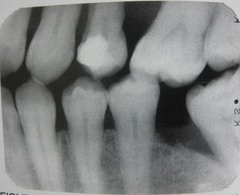

vertical bone loss

Front

Back

horizontal bone loss